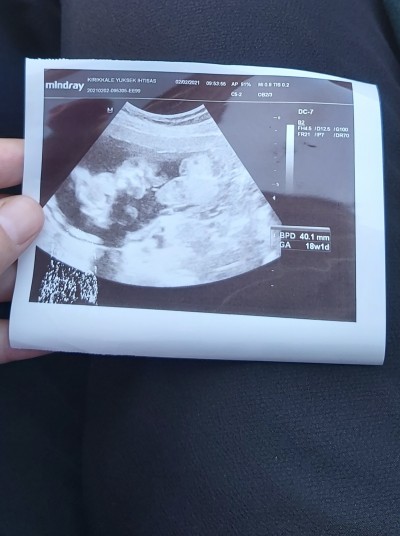

Kizlar doktor bu fotoğrafı verdi ama bu neresi bebeğin

Kaç haftalık ki bebiş çözemedim valla:D

18 haftalık ya bende çözemedim

Haftası da büyükmüş ama bilemedim kız:))

Bende bilemedim kiz dedi bacak arasi ki ki acaba belli değil hic

Sağdaki bebek galiba kiz dedi cinsiyeti acaba biraz alttan bacak arasini mi çekmeye calisti anlayamadım bende bisey

Cenin pozisyonda bebegin yüz üstü duruyo

Hm bacak arasini çekmeye çalışmış galiba hafif asagidan